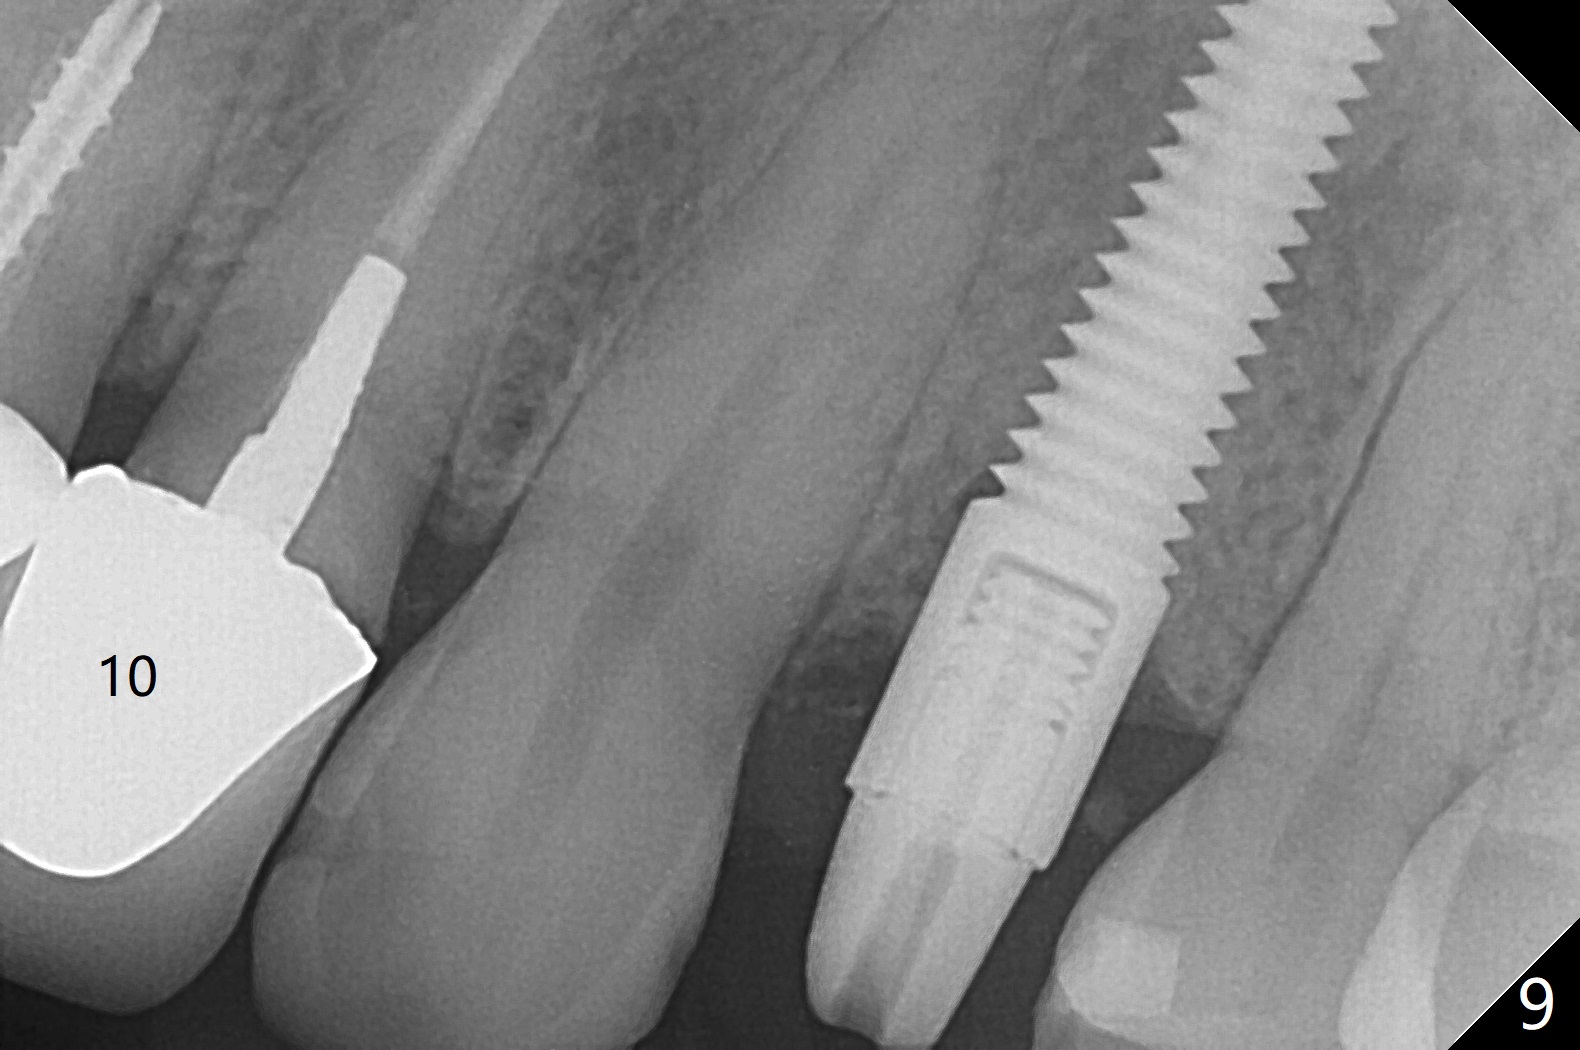

When the 44-year-old woman returns, the crown dislodges from #9 with palatal porcelain chip (Fig.1). Although the post is in place as compared to its dislodgement last visit, it is short and pointed (Fig.2,3 P). Because of the anterior deep bite (Fig.4), an implant restoration may not provide advantage; a new build-up is fabricated (B-U) for a new crown (Fig.5-6). The existing crown is reinserted for shade comparison (Fig.7 C). The gingiva at #8 and 9 is healthy, whereas that at #10 is not (Fig.8). PA taken 5 months later shows that the crown at #10 looks normal (Fig.9).